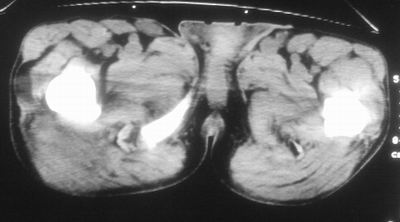

标题: CT16837:M63Y,右臀部巨大软组织包块

患者,男,63岁,自诉3个月前发现右臀部包块,触及疼痛,治疗后缩小。前天突然增大。无高热病史。

考虑-----右臀大肌,臀中肌---感染性病变可能性大。

病灶内部可见出血,首先考虑急性出血性病变.血肿?

给个骨窗,判断一下肿块是否与髂骨有关,肿块内出血是肯定的,至于是感染形成的脓肿还是起源于肌肉或纤维组织的肉瘤则难以确定,不过从影像上看,包膜完整,且环形增厚,病灶下部见斑片状底密度坏死,个人倾向感染可能性大

肌间隙明显混浊,三个月前治疗有缩小,支持考虑臀大肌下脓肿伴出血,肿瘤如果出现瘤内出血的话瘤外边界应该较清楚,现在表现为一种恶性征像,但骨质无明显异常,且臀小肌边界清楚,不符合恶性表现.